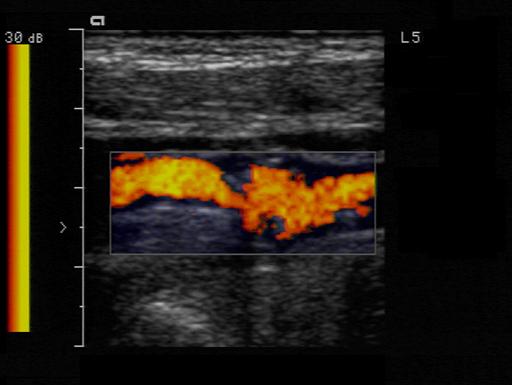

Occlusion

Complete blockage

- Best used with the terms probable & total

- Complete filling of the vessel internal area with heterogeneous material

- No blood flow

What must one do in calling an occlusion

sensitize the equipment before doing so

Decrease PRF

Increase color gain, use power Doppler

Mosaic

A mottled appearance caused by turbulent flow

Jet

A localized area of higher flow through and after an area high grade stenosis